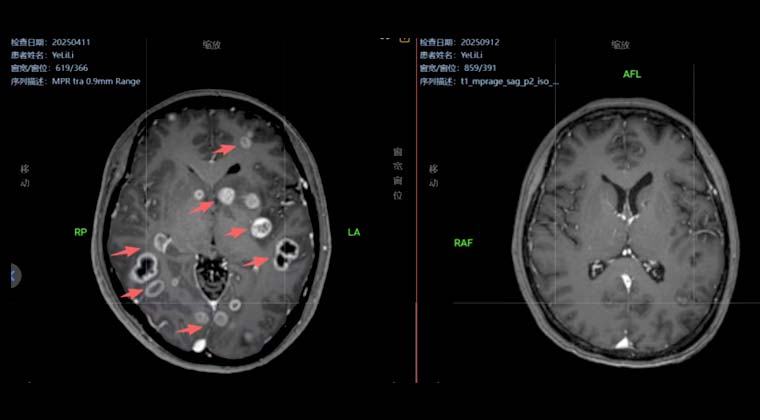

Пациентка, 76 лет

Диагноз «рак носоглотки» был поставлен 5 лет назад; стандартная химиолучевая терапия не проводилась, лечение осуществлялось самостоятельно. Месяц назад головные боли стали прогрессирующими и невыносимыми, сопровождались опущением левого века и снижением слуха.

Пациентка и семья попросили облегчить симптомы и уменьшить боль, отказавшись от химиотерапии. Была проведена паллиативная лучевая терапия локального очага опухоли. Опухоль оказывала давление на продолговатый мозг, поэтому была назначена доза 50 Гр / 25 фракций.

После 7 сеансов лучевой терапии опухоль значительно уменьшилась (на изображении область опухоли обозначена красной сплошной линией), головная боль облегчилась. У пациентки повысилась уверенность в лечении. План лучевой терапии был скорректирован для облучения шейной зоны лимфатического дренажа, и в итоге локальная опухоль получила суммарную радикальную дозу 70 Гр.

До лечения

После 7 сеансов лучевой терапии